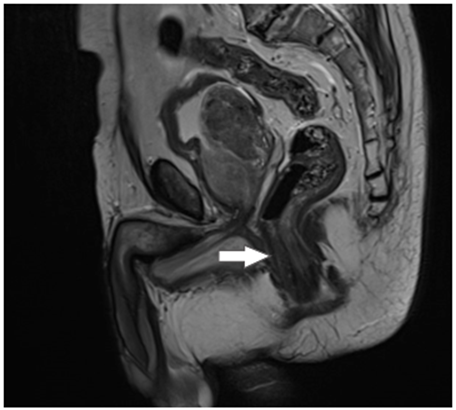

Así mismo, se realizó una RNM para evaluar extensión del tumor, donde se observa marcado engrosamiento de la pared rectal, sin tumor residual, producto del procedimiento quirúrgico y la reacción inflamatoria reparativa (Figura 2). La colonoscopia de control solo evidenció cicatriz sin cambios displásicos (Figura 3).